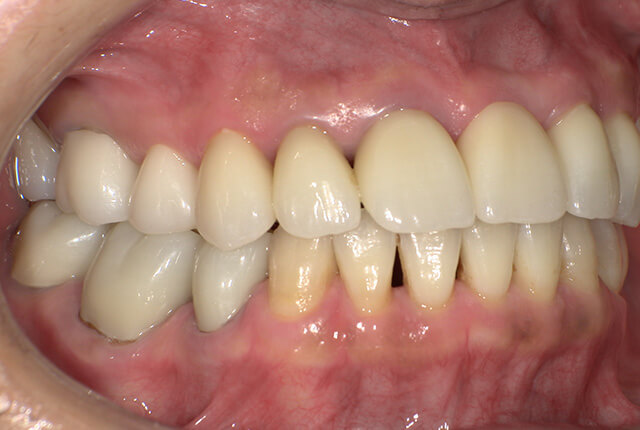

90分の治療で銀歯の状態からキレイな状態になります。噛み合わせの調整や審美面も使用しながら合わせます。

良く噛めて安心と、ご満足いただき大変嬉しく思います。笑顔も一層素敵になりました。

| 治療内容 | 欠損部インプラント 不正咬合に対し不良補綴のやり直しと合わせて咬合再構築 |

| 治療計画 | 欠損部インプラント 不良補綴のやり直しと欠損部インプラント。 咬合の再構築、なるべく歯を残せる様に治療計画を立案。 |